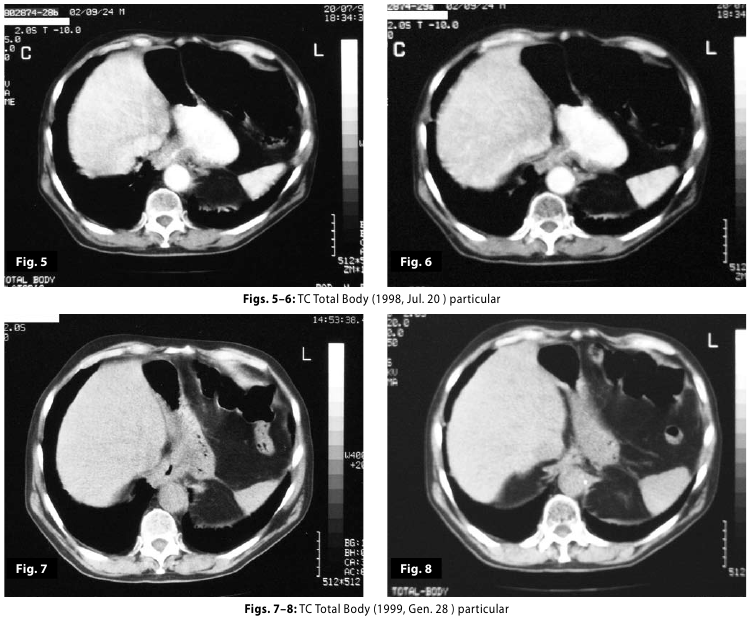

Figure7

Figure8

Figure7-8

Figure5-6-7-8